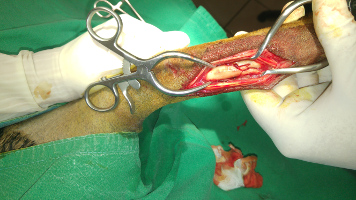

Chirurgies orthopediques:

-réduction des fractures (pose divers implants plaques broches etc),

-rupture du ligament croisé (prothèse ligamentaire)